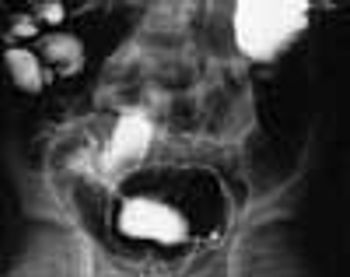

This 8-month-old girl presented with chronic constipation, which had begun during the neonatal period. She had her first bowel movement at 72 hours of age. Since then, she has had bowel movements once every 3 to 4 days. Her stools are pelletlike. Results of thyroid function tests done when she was a neonate were normal.

A 6-year-old boy presented with bloody diarrhea; fatigue; decreased appetite; weight loss; and occasional, mild abdominal pain for the past 2 months. The child had 6 to 8 bowel movements daily, 1 or 2 of which occurred at night.

A 6-year-old boy is brought for evaluation of bloody diarrhea, fatigue, decreased appetite, weight loss, and occasional, mild abdominal pain of 2 months' duration. The child had 6 to 8 bowel movements daily, 1 or 2 of which occurred at night.